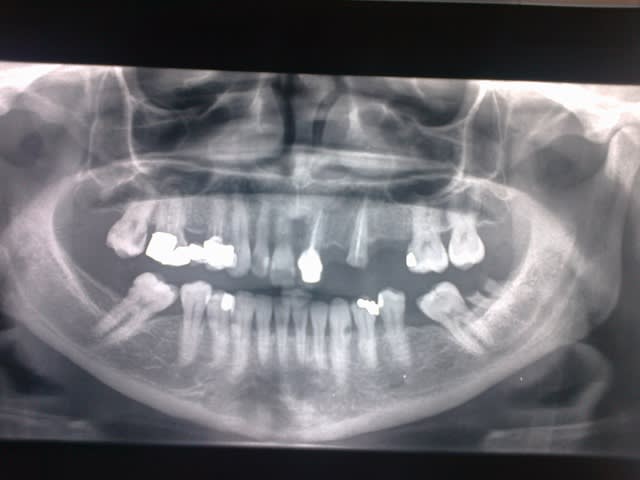

la voila la pano:)

merci pour l'astuce de google chrome ça a marché

de rien...réessayes sans compresser ton image parce que là...on a le format timbre poste...

c'est pas l'idéal pour étudier correctement le cliché...;-)

deuxième question: distance entre 23 et 26 en mm...juste pour savoir si tu as la place pour 1 ou 2 implants...(je me méfie des panos qui ont tendance à superposer dans ces secteurs et donc "écraser" les distances réelles)

la distance entre la 23-26 est suffisante pour 2 PM.ya pas une version mesiale de la 26

16 -18 mm je crois.elle porte encore une PAP(stellite) a cet endroit